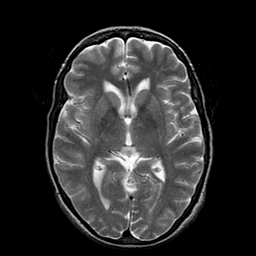

Metastatic Adenocarcinoma of the Colon: T2-weighted MR -- Slice #12

[Home][Help][Clinical] Slice 12